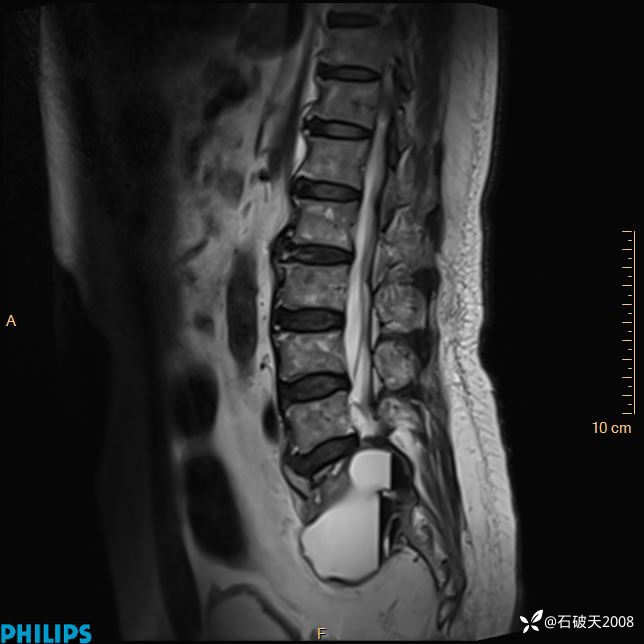

2023年3月份MRI影像

T1矢状位